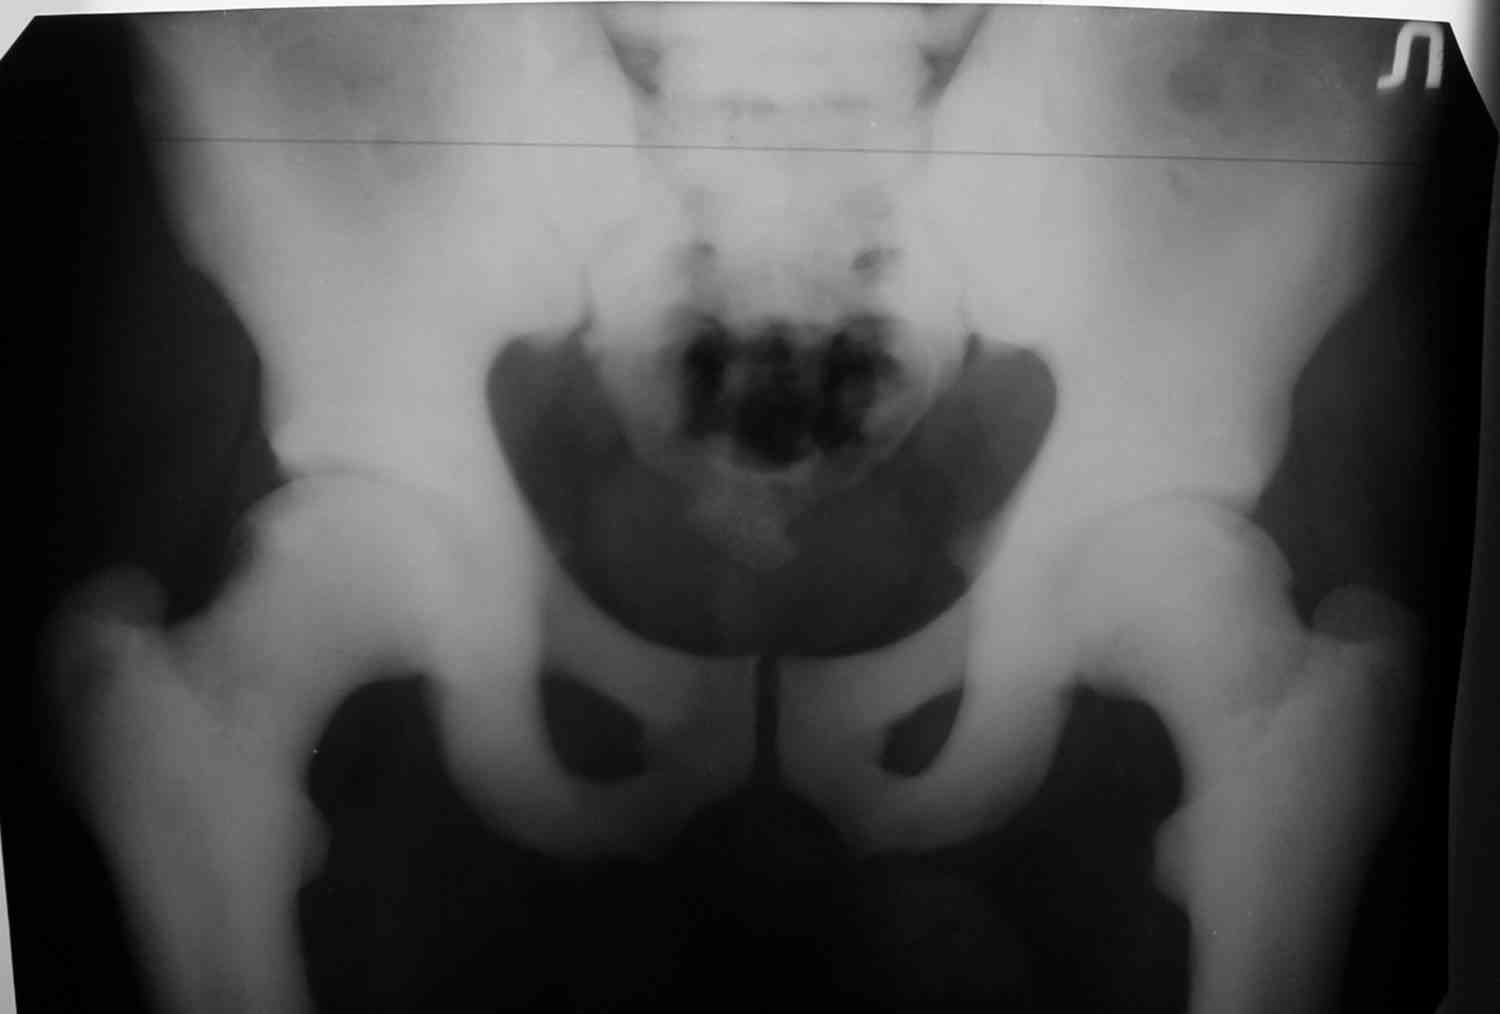

Уважаемый Константин Иванович! Полностью согласен с проф. Михайловым,

данный случай не похож на мраморную болезнь, при которой имеется

резкое, строго симметричное и генерализованное уплотнение костной

ткани (остеопетроз), и кость оказывается построенной преимущественно

из гомогенного компактного костного вещества. Для примера привожу

случай из архива нашего института (бедренные, плечевые кости и таз,

рис 1,2,3)